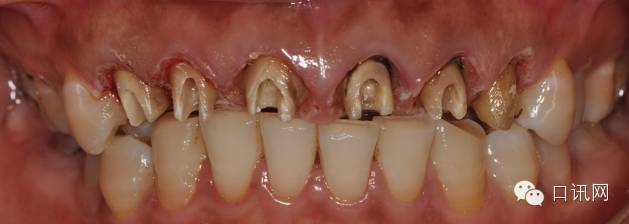

查:11,12,13,21,22,23为烤瓷联冠修复体,冠边缘不密合,冠边缘位于龈下 2mm,牙冠边缘发黑,牙龈红肿,叩诊(士),无松动熟练掌握口腔内科治疗,21唇侧有瘘管,轻压有溢出物中华人民共和国执业医师法

原金属烤瓷冠

原金属烤瓷牙咬颌观